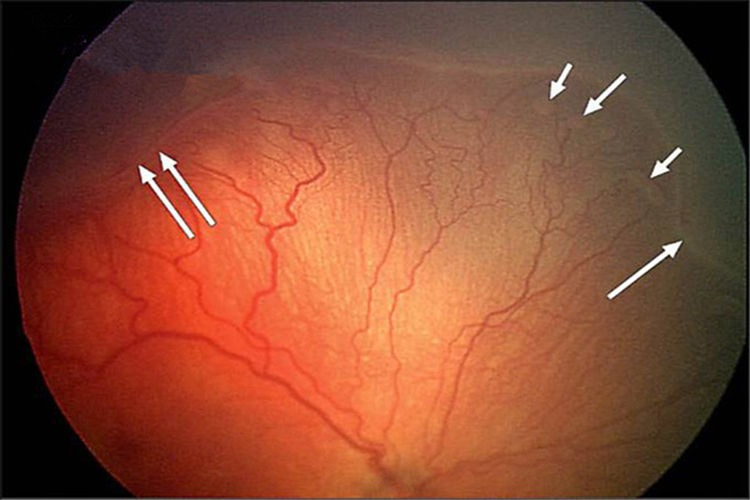

原發性視網膜脫落眼底